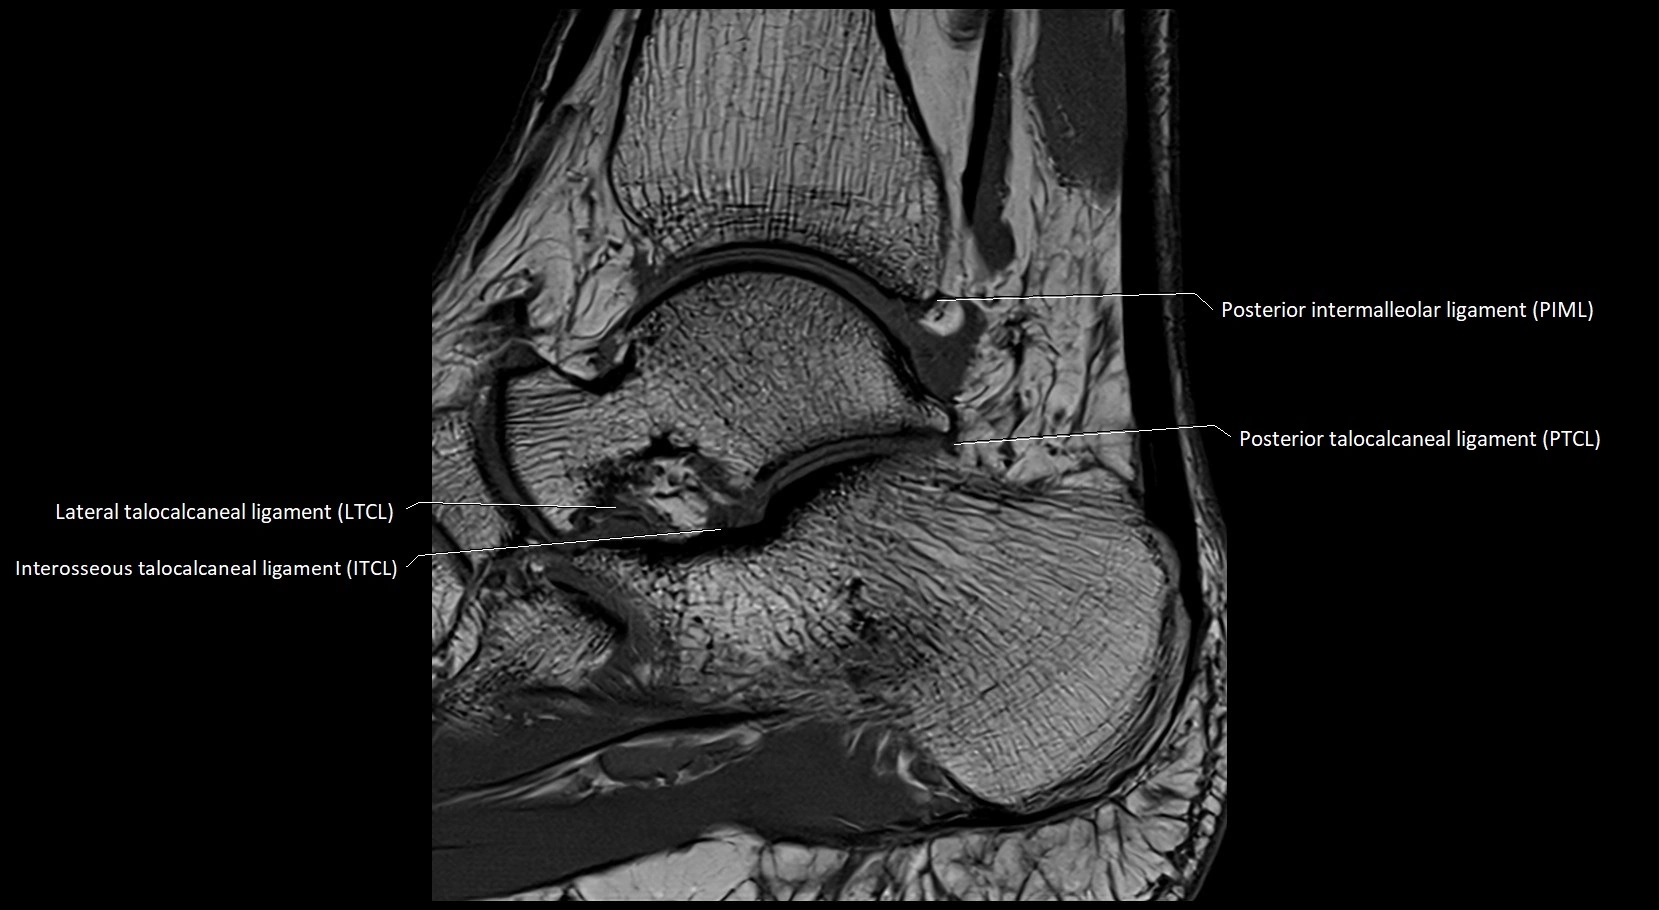

MRI image

image